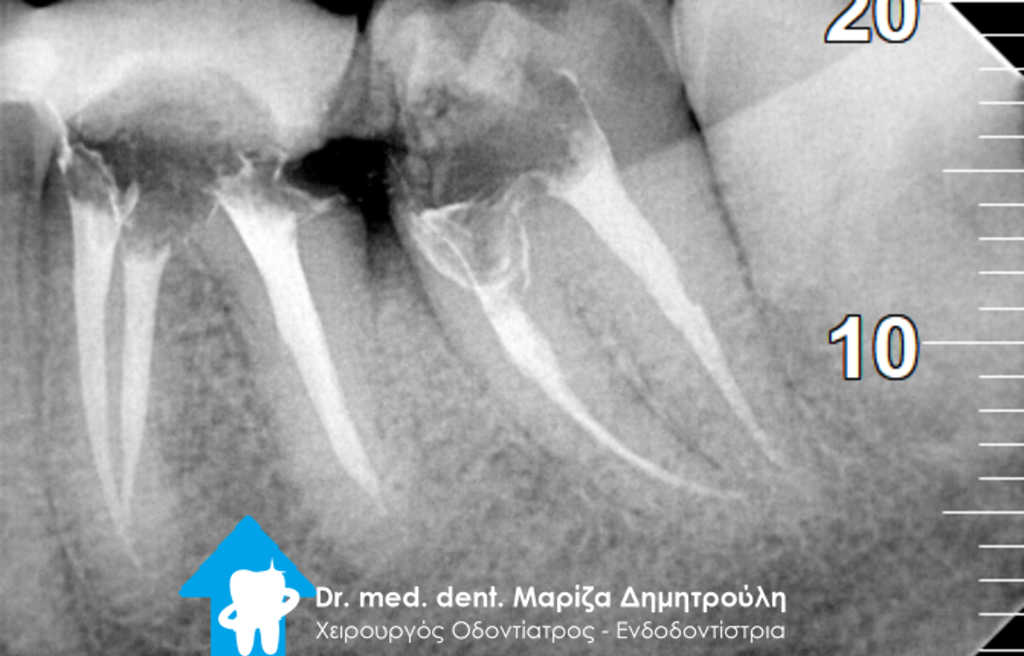

Ο ασθενής τον τελευταίο καιρό ταλαιπωρείται από έντονα συμπτώματα πόνου στη δεξιά μεριά της κάτω γνάθου. Σύμφωνα με τα λεγόμενα του στο δόντι είχε πραγματοποιηθεί απονεύρωση και στη συνέχεια τοποθετήθηκε ένθετο για την αποκατάσταση του οδοντικού ελλείμματος. Κατευθείαν πραγματοποιήθηκε ακτινογραφία του δοντιού, η οποία έδειξε την ατελή έμφραξη των ριζικών σωλήνων του δοντιού, καθώς το υλικό έμφραξης δεν εκτεινόταν σε όλο το μήκος των ριζών του δοντιού. Η κλινική εξέταση επιβεβαίωσε την έντονη αντίδραση του δοντιού κατά την επίκρουση του.

Μετά από συνεννόηση με τον ασθενή αποφασίστηκε η απομάκρυνση του ένθετου και η επανάληψη της απονεύρωσης. Πράγματι μετά τη χορήγηση τοπικής αναισθησίας, απομακρύνθηκε το ένθετο, εντοπίστηκε και αφαιρέθηκε η παλιά απονεύρωση από το εσωτερικό των ριζικών σωλήνων. Στη συνέχεια τοποθετήθηκε φάρμακο στις ρίζες του δοντιού και η χημικομηχανική επεξεργασία του δοντιού συνεχίστηκε στο επόμενο ραντεβού.

Λόγω του οιδήματος στην περιοχή το δόντι δεν εμφάνιζε συμπτώματα πόνου στο τρίτο ραντεβού, οπότε και ολοκληρώθηκε η ενδοδοντική θεραπεία με την έμφραξη των ριζικών σωλήνων με το υλικό της γουταπέρκας.

Η τελική αποκατάσταση του δοντιού πραγματοποιήθηκε με μεταλλοκεραμική στεφάνη δοντιού για την καλύτερη προστασία του ταλαιπωρημένου δοντιού.